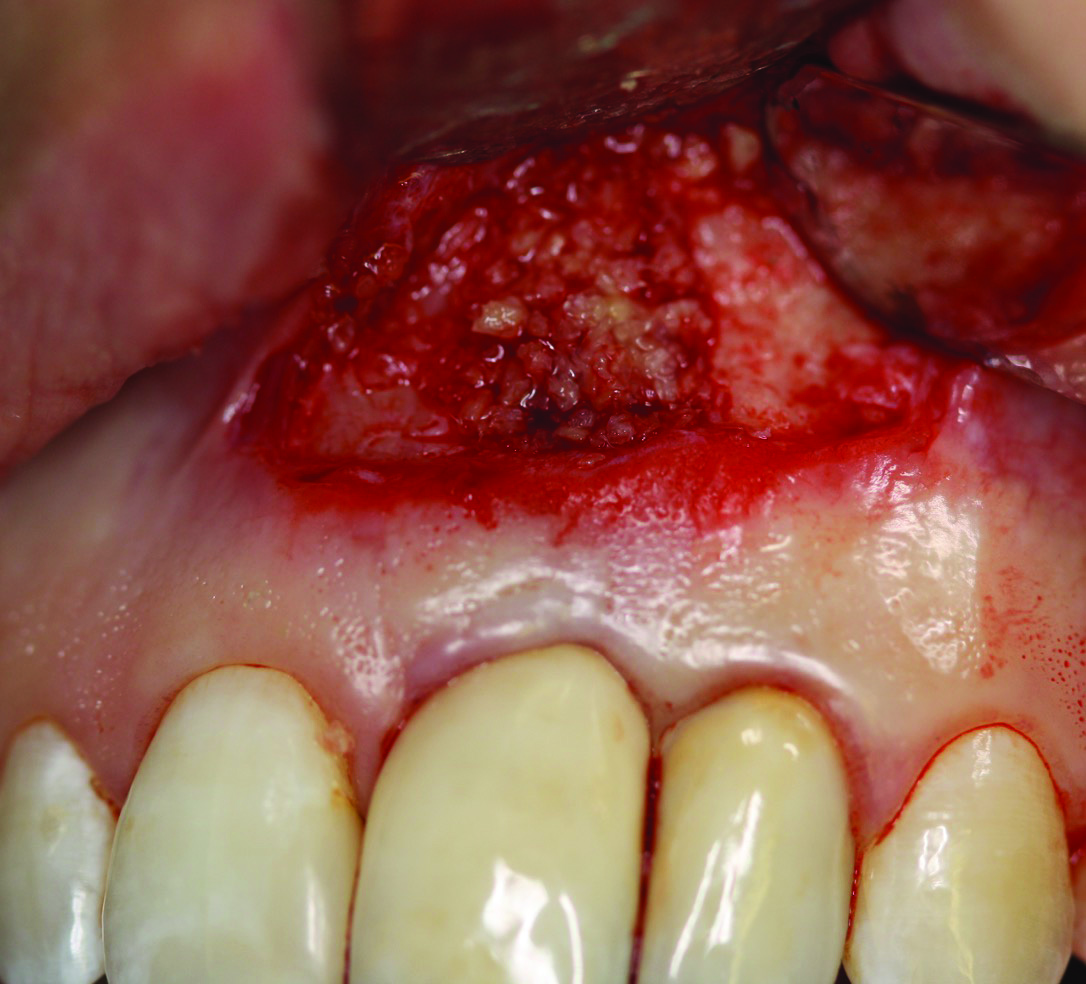

Fig 3 and Fig 4. Case 2: Initial clinical presentation showing implant No. 6 with RPI, having been impacted by fractured tooth No. 5 (Fig 3); radiograph showing fractured tooth No. 5 with periapical lesion extending to the distal aspect of implant No. 6 (Fig 4).

Fig 4. Case 2: Initial clinical presentation showing implant No. 6 with RPI, having been impacted by fractured tooth No. 5 (Fig 3); radiograph showing fractured tooth No. 5 with periapical lesion extending to the distal aspect of implant No. 6 (Fig 4).

Patient 2: A 63-year-old healthy male patient presented with implant No. 6 exhibiting RPI, having been affected by previously endodontically treated and fractured tooth No. 5 (Figure 3 and Figure 4). The implant had probing depths ranging from 4 mm to 10 mm (Table 1) with the most severe bone loss at the distal aspect of implant No. 6 (Figure 3 and Figure 4).